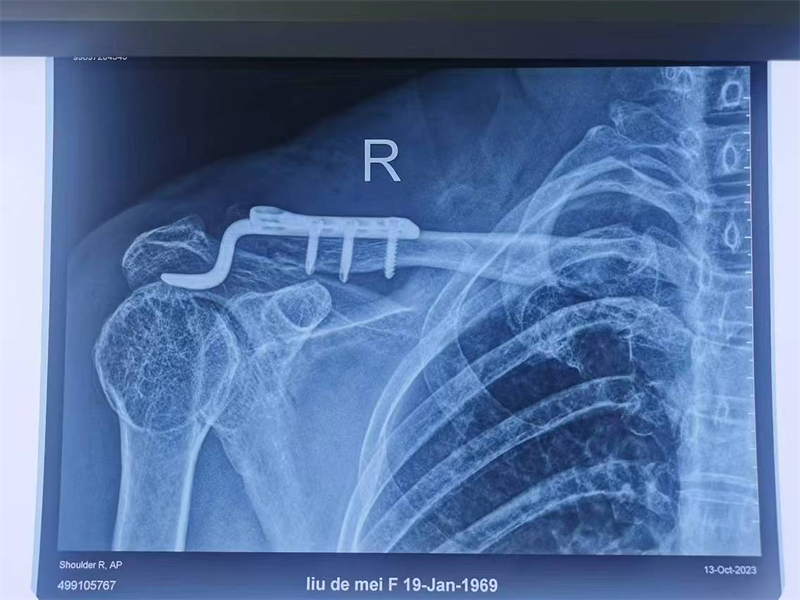

近期,寿光和信医院骨外科采取肩锁关节脱位切开复位袢钛板内固定术,一锚双袢固定,为肩锁关节脱位患者提供了一种全新的治疗选择。

肩锁关节脱位是创伤骨科的一种常见疾病,而肩锁关节脱位切开复位袢钛板内固定术则为这些患者带来了曙光。术后功能良好,肩锁关节脱位Ⅲ度新鲜损伤生物重建有优势,美容缝合,不用二期取出内固定,简单、实用、美观、功能良好,比钩钢板固定有很大优势。通过及时的治疗和正确的康复措施,患者完全可以告别肩锁关节疼痛带来的困扰,重新拥有健康和快乐的生活。